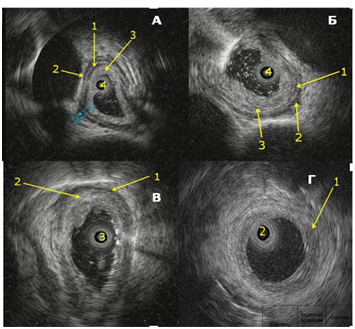

Digital Formats: During EUS, damaged esophageal wall layers were highly echogenic with a heterogeneous echo structure. Increased thickness and impaired differentiation of the contours and boundaries of the damaged esophageal wall layers were noted. Based on changes in their structure during EUS, we developed the following grading for damage to the muscular layers of the esophageal wall: grade 4a, 4b, 4c, 4d (Fig. 1 and Fig. 2).

Fig 1:

Fig 2. A – Grade 4a esophageal reflux disease. 1 – Impaired differentiation of the mucosa and submucosal layers, 2 and 3 – thickened circular and longitudinal muscle layers, 4 – ultrasound mini-transducer.

B – Grade 4b esophageal reflux disease. 1 – Partially damaged circular muscle layer, 2 – intact longitudinal muscle layer, 3 – damage extending to the submucosal and circular muscle layers, 4 – ultrasound mini-transducer.

B – Grade 4c esophageal reflux disease. 1 – Partially damaged longitudinal muscle layer, 2 – damage extending to the submucosal, circular muscle, and partially longitudinal muscle layers, 3 – ultrasound mini-transducer.

D – Grade 4d esophageal reflux disease. 1 – damage extending to all layers of the esophageal wall, 2 – ultrasound mini-transducer.